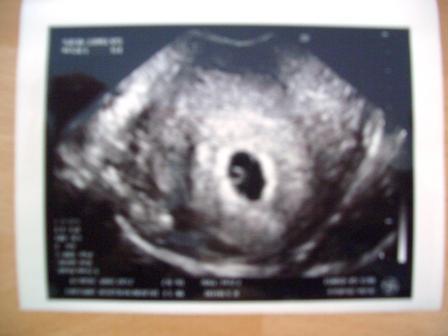

Hier noch das Bild! LG Bea

Oh wie süss Ein tolles Bild ... wie aufregend was wieder alles ist nicht wahr? Man freut sich über jedes Foto das man bekommt LG Jessi

Ohhh das ist aber ein schönes Bild. lg Steffi